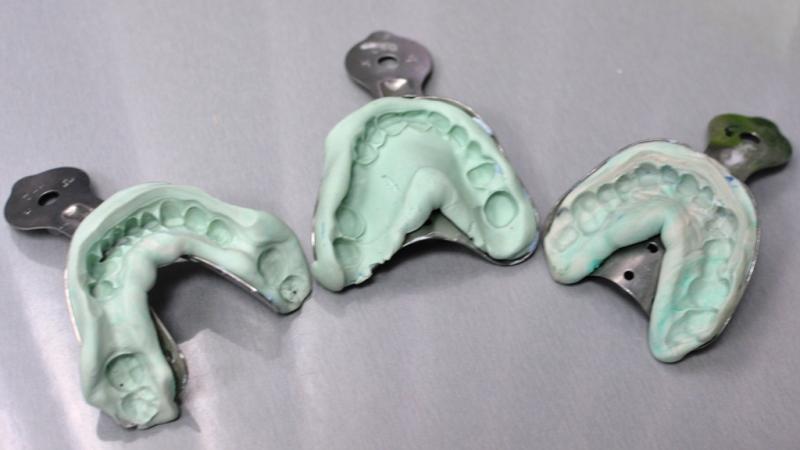

Для получения качественной цельнолитой коронки необходимо пройти несколько этапов производства. Сначала проводится осмотр и санация ротовой полости, а затем делается слепок зуба, который требует протезирования. Стоматологи используют безопасные слепочные массы из силикона, которые точно отображают анатомические особенности челюстного аппарата. Для комфорта пациентов и привыкания к протезам, им устанавливают временные коронки. Затем создается гипсовая модель будущего протеза, на основе которой изготавливают восковую заготовку, затем заменяемую на металлический сплав.

image